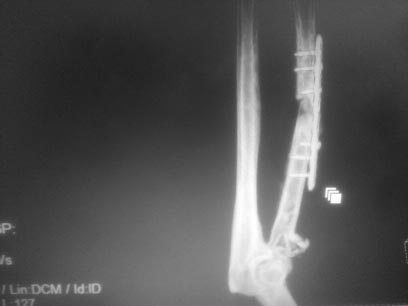

Эссекс-Лопрести с переломом диафиза лучевой кости.

Пациент муж 48 лет, г.Москва 9.04.17 г травма оскольчатый перелом диафиза, многооскольчатый перелом головки лучевой кости с повреждением дистального радиоульнарного сочленения и межкостной мембраны (Эссекс-Лопрести с переломом диафиза лучевой кости).

Обратился в клинику через 2 часа после травмы, рекомендован одномоментно остеосинтез диафиза и протезирование головки лучевой кости. Пациент от лечения в клинике (частная) отказался и обратился в одну из гор больниц. Был выполнен остеосинтез диафиза лучевой кости пластиной, головку лучевой кости трогать не стали. После операции вновь обратился в клинику, предложено протезирование головки лучевой кости. От операции в клинике отказался (вернее отказалась мать,очень зависит от мнения матери) и обратился в частную VIP клинику, где был выполнен остеосинтез многооскольчатого перелома головки лучевой кости винтами (довольно впечатляюще) и временная фиксация спицами костей предплечья.

В настоящее время вновь обратился к нам в клинику со следующей клинической картиной: Локтевой сустав - дефицит разгибания 30 градусов, сгибания 20 градусов (не особенно беспокоит), отсутствие ротации предплечья(беспокоит), боли в лучезапястном суставе. При осмотре деформация предплечья, небольшая патологическая подвижность в с/3 предплечья, незначительное ограничение движений в лучезапястном суставе, но боли при движениях (преимущественно при девиации).

На выполненом МСКТ (снимки отдельных сканов прилагаю) несращение диафиза лучевой кости, деформация оси 20 градусов (на первых снимках после операции ось нормальная), резорбция вокруг проксимальных винтов, значительные гетеротопические оссификаты вокруг головки лучевой кости, ее консолидация с небольшим смещением, неконгруэнтность в лучелоктевом сочленении. Планируемые варианты лечения:

1 Реостеосинтез диафиза лучевой кости пластиной с костной аутопластикой, после (в случае) консолидации перелома вторым этапом протезирование головки лучевой кости.

2 Одномоментно реостеосинтез диафиза лучевой кости пластиной без костной пластики и протезирование головки лучевой кости, с компенсацией длины лучевой кости за счет за счет протеза головки.